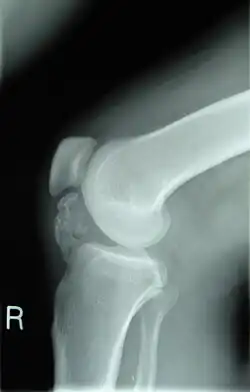

Lateral radiograph of the knee demonstrating ossification in the peritendinous tissues in a patient with osteochondroma.